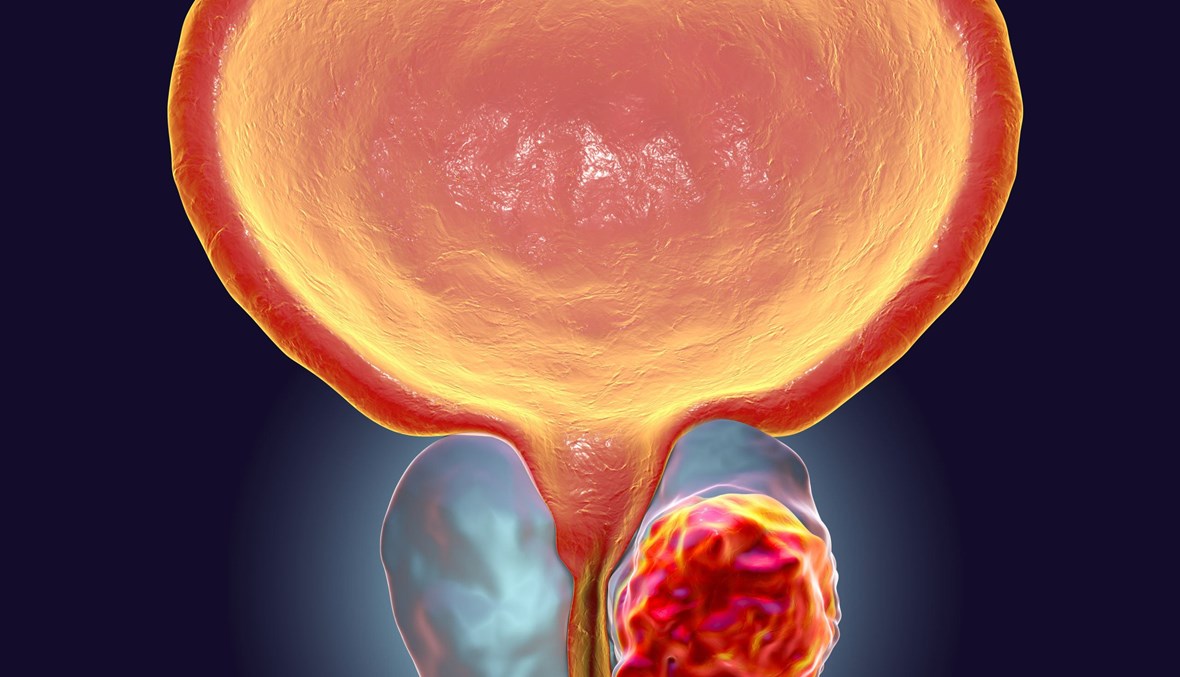

يُصيب سرطان البروستات نسبة لا بأس بها من الرجال، تبلغ ما يقرب من 25 % من مرضى السرطان، ممّا يدعو أولئك المصنّفين ضمن الأكثر عرضة للإصابة بسرطان البروستات إلى إعادة النظر في عاداتهم التي يتّبعونها، وفي نمط حياتهم، ليحاولوا الحدّ من خطر تطوّر المرض لديهم، وفق ما نشر في medisite.

وعلى الرغم من أن الإصابة به تعتبر نادرة قبل سنّ الخمسين، فإن الخطر يزداد مع التقدّم بالسنّ، في الوقت الذي تزداد فرص تخطّي المرض لدى تشخيصه في مرحلة مبكرة، وتتعدّى نسبة الـ90 في المئة.

وبحسب إحدى الدراسات الحديثة، يُمكن للرجال الذين يواجهون خطر الإصابة بسرطان البروستات، بسبب العامل الوراثيّ، أن يخفّضوا الخطر، فيحدّوا من تطور المرض بنسبة 50 في المئة بفضل نمط حيّاة صحيّ.

فقد تبيّن في الدراسة المشار إليها أن الرجال الذين يتّبعون عادات سليمة، يُمكنهم أن يحدّوا من خطر تطوّر المرض بشكل يهدّد حياتهم بنسبة 50 في المئة من خلال العادات السليمة، خصوصاً أنّ وجود العامل الوراثي يزيد الخطر إلى حدّ كبير. وبالتالي، يمكن من خلال التغييرات في نمط الحياة والتشخيص المبكر والعلاج المبكر مواجهة الخطر الوراثيّ بشكل أفضل.